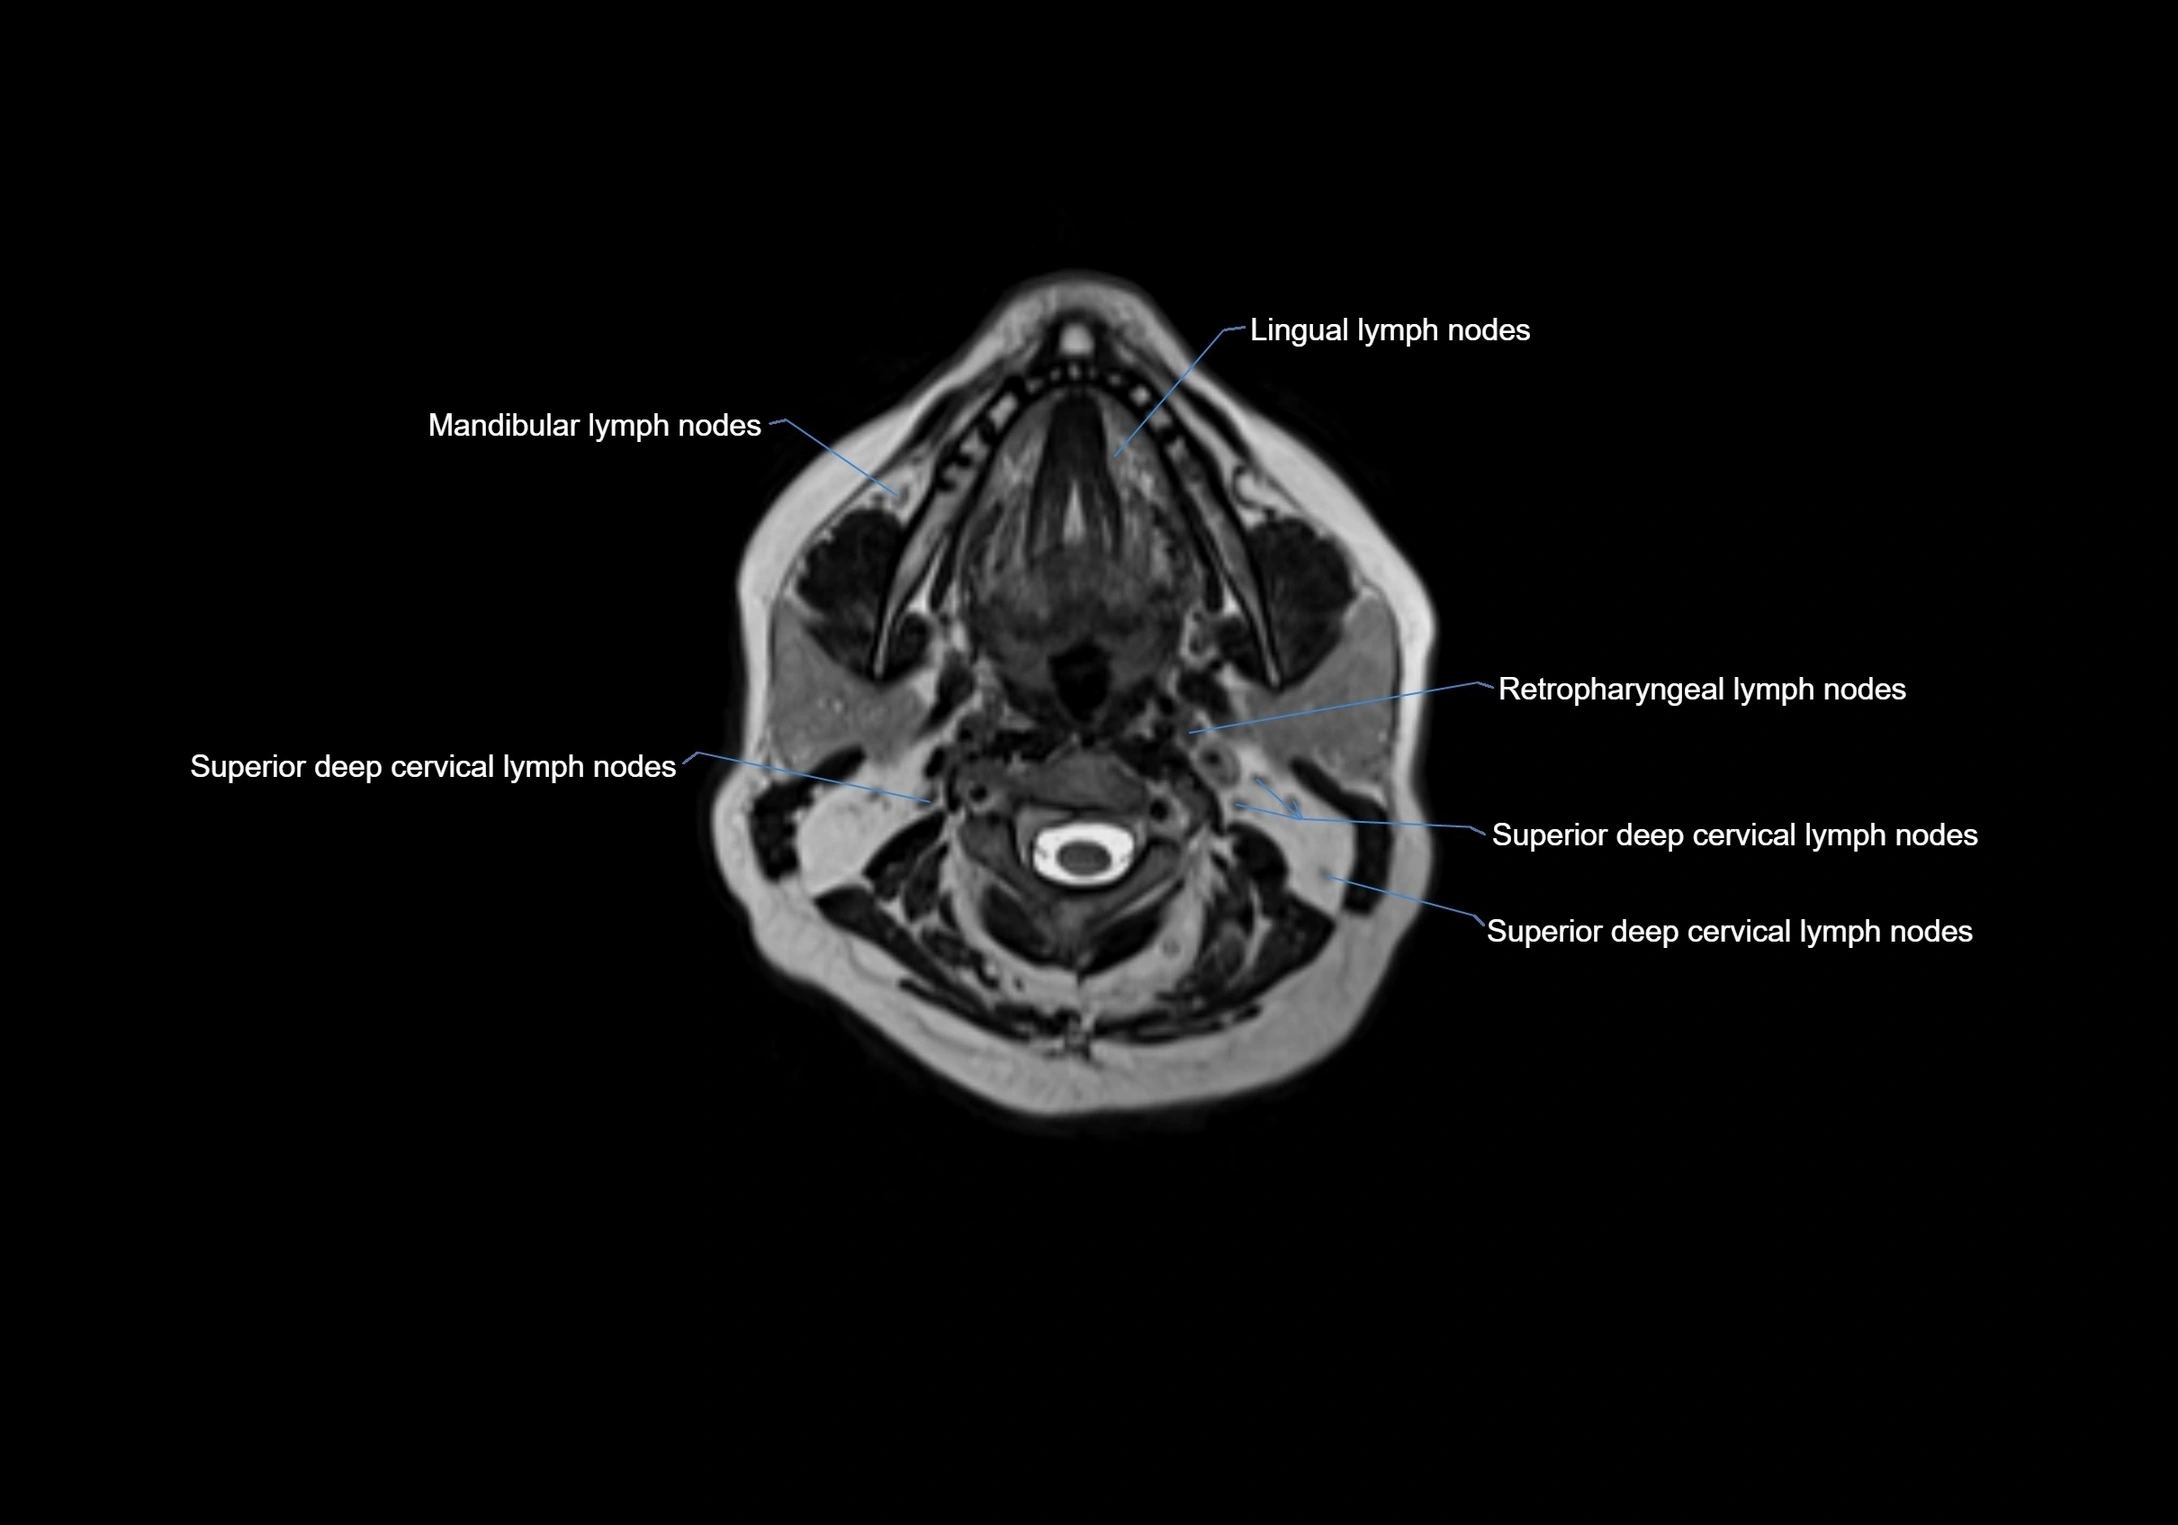

Accessory lymph nodes are small, secondary lymph nodes located along the main facial and cervical lymphatic chains, often adjacent to primary lymph nodes, such as preauricular, submandibular, or occipital nodes. They are typically less than 5 mm in diameter, embedded within subcutaneous fat or connective tissue, and may be variable in number and location. These nodes provide additional filtration and immune surveillance for lymph collected from the face, scalp, and neck regions. Accessory lymph nodes are usually non-palpable in healthy individuals but may enlarge in response to infection, inflammation, or metastasis, making them clinically significant.

Location

• Found along primary lymph node chains, including preauricular, submandibular, parotid, and occipital regions

• Embedded in subcutaneous fat or superficial fascia, often lateral or posterior to primary nodes

• Variable in number; may occur unilaterally or bilaterally, depending on individual anatomy

MRI images